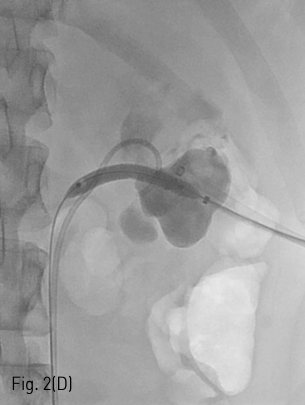

환자는 왼쪽 신장의 isolated calyx에는 8.5Fr. drainage catheter가 insertion 되어 있고 left renal pelvis에는 double J stent가 insertion 되어 있는 상태로 prone position을 취하였다. 기존의 drainage catheter에 0.035inch 유도 철사(Terumo, Tokyo, Japan)를 insertion 하고 catheter는 제거한 후 8Fr. Sheath(Boson, Shrewsbury, USA)를 삽입하였다. 조영제(Visipaque, GE healthcare, Chicago, USA)를 주사하여 tubogram을 시행하였고 isolated calyx 와 콩팥깔때기와의 연결성은 없었다. (Fig.1B) 초음파 유도 하에 21G 천자바늘(Cook, Bloomington, USA)로 isolated calyx를 천자하고 X선 투시하에 천자바늘을 콩팥깔때기에 insertion 되어 있는 double J catheter를 향해 진입시켰다. (Fig. 2A, B) 천자바늘의 속심을 제거한 후 X선 투시하에 조영제를 주사하여 isolated calyx를 지나 콩팥깔때기가 천자된 것을 확인하고 0.018inch 유도 철사(A & A, Gyeonggi, Korea)를 넣었다. (Fig. 2C) 이후 천자바늘을 제거하고 단일 막대 접근 장치(yellow sheath; A & A, Gyeonggi, Korea)를 이용하여 접근로를 확보했다. 유도 철사와 metal stiffening inner cannula를 제거하고 0.035inch 유도철사(Terumo, Tokyo, Japan)를 넣고 6mm x 4cm balloon(Boson, Shrewsbury, USA)을 이용하여 isolated calyx와 콩팥깔때기 간 neoinfundibulum 을 재건하였다. (Fig. 2D) 삽입되어 있는 유도 철사를 통해 isolated calyx, neoinfundibulum 그리고 콩팥깔때기를 차례로 통과하도록 10.2Fr. nephrostomy catheter(Cook, Bloomington, USA)를 위치시켰다. (Fig. 2E) 4일 후 기존의 10.2Fr PCN catheter insertion site를 통하여 10Fr sheath(Terumo, Tokyo, Japan)를 insertion 한 뒤 0.035inch 유도철사(Terumo, Tokyo, Japan)를 방광까지 진입시킨 뒤, 26cm 7Fr double J stent(Boson, Shrewsbury, USA)의 원위부는 방광에 위치시키고 근위부는 isolated calyx에 위치시켰다.(Fig. 3) 이후 isolated calyx로의 접근로에는 10.2Fr. nephrostomy catheter(Cook, Bloomington, USA)를 삽입하고 시술을 종료했다.

Fig 2D

(D) Balloon dilatation was performed.